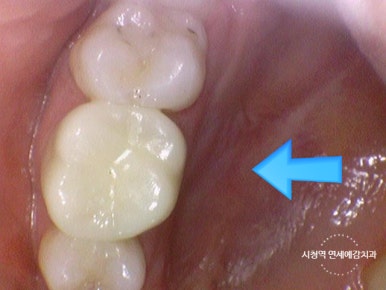

지르코니아 크라운 치료 전 후

지르코니아 크라운 치료 전후